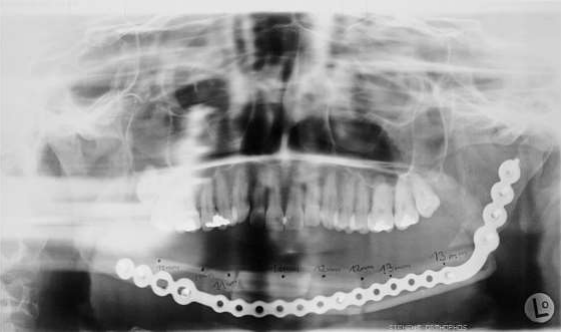

Fig 5:Juni 1997: resection of the lower jaw regio 46-37, plate for reconstruction, AAA-bone histology: ossyfying fibroma turned into osteosarkoma grade III, resection non in sano

Figure 5